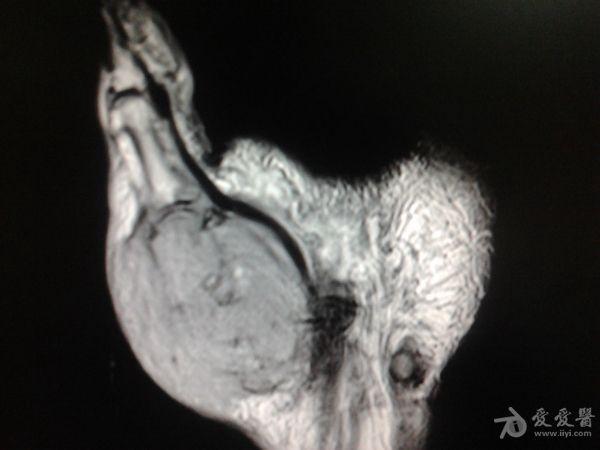

右第一掌骨、大多角骨肿瘤

男性患者,81岁,右手肿痛3个多月。无任何其它症状。体查:右手第一掌骨部肿胀明显,第一指活动受限,余四指活动可,腕关节活动小部分受限,活动时会痛。影像学检查如下。活检示:弥漫性大B细胞淋巴瘤。大家看看需不需要截肢?现在有人主张手术;有人主张不手术,直接化疗。大家有什么看法?